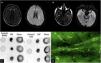

The patient is a 28-year-old man with no history of chronic disease. Two weeks before presentation, he was diagnosed with mild COVID-19. During home isolation, he presented an altered mental state characterized by incoherent speech, somnolence, auditory hallucinations, suicidal ideation, and generalized tonic-clonic seizures. At the evaluation, he presented front-orbital syndrome characterized by catatonic symptoms; no neck stiffness or focal signs were found. The initial laboratory and cerebrospinal fluid (CSF) were normal; the FilmArray meningitis/encephalitis panel (BioFire Diagnostics, Salt Lake City, UT) was negative. However, the brain's magnetic resonance imaging (MRI) revealed hyperintensities in the bilateral anterior cingulate cortex and temporal lobes [Fig. 1A,B]. Electroencephalogram reported subcortical dysfunction in frontal, temporal, and occipital regions; due to suspected viral encephalitis, acyclovir and levetiracetam treatment were started. However, two days later, he presented status epilepticus requiring orotracheal intubation. Due to his bad evolution, further studies of the CSF were requested, SARS-CoV-2 PCR and anti-SARS-CoV-2 IgG (enzyme-linked immunosorbent assay) were negatives; immunoblotting revealed IgGs against neuronal proteins 150 kDa and 75−50 kDa (NMDAR and GAD65/67), dot-blotting was positive for NMDA, and GAD65 antigen and tissue-based assay with direct immunofluorescence revealed intracellular and cell-surface antigens [Fig. 1C,D]. All laboratory supplies were purchased from Santa Cruz Biotechnology, Inc. Malignancy, systemic autoimmune disease and infections were ruled out.

(A) MRI of the brain in T2 FLAIR and diffusion-weighted imaging showing hyperintensities in the bilateral anterior cingulate cortex and (B) bilateral temporal lobes (white arrows). (C) Dot blot (1:1,000 dilution); revealing positivity for the presence of GAD65 and NMDA antigens in the CSF. (D) Tissue-based assay in CSF with direct immunofluorescence showing intracellular and cell-surface antigens (GAD65, NMDA).